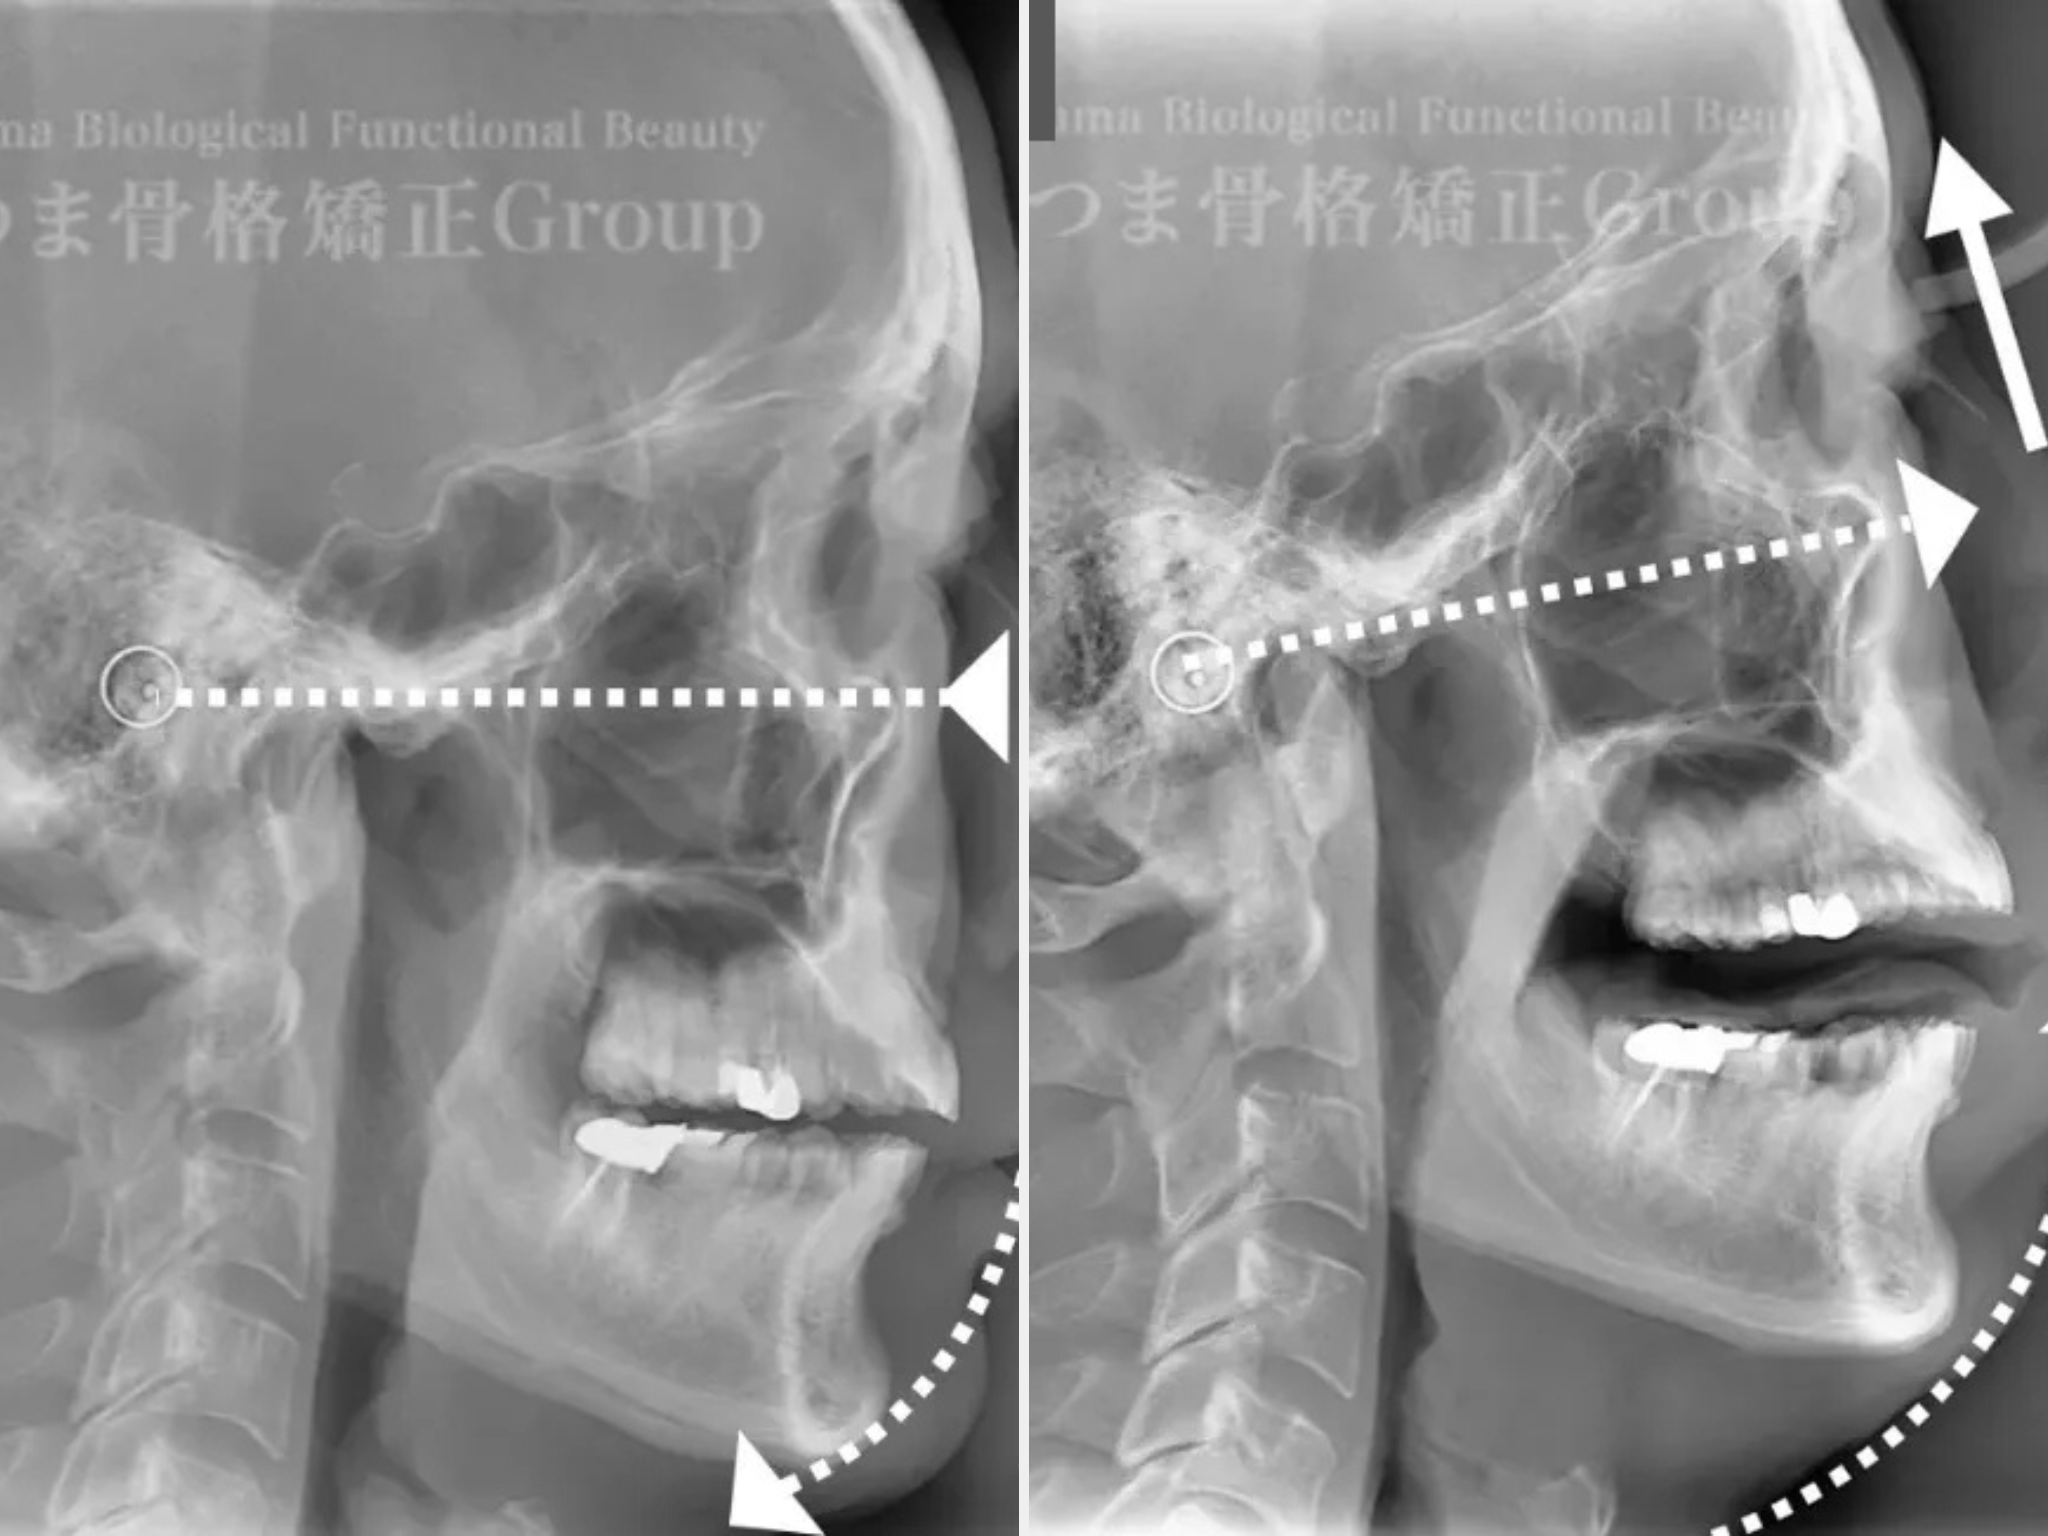

レントゲン写真(X-ray images)を用いた骨格分析を行っています。

顔や頭蓋、首まわりの骨格の位置や傾き・左右差をレントゲン写真で確認し、改善の方向性を明確にします。

歯科矯正でも使用されるセファロスタンドにて頭部と耳を固定した位置で正面の顔横顔を二次元的に分析します。

※頭部と耳を固定することで角度と距離の基準が決まります。

歪み検査は頭部と耳を固定して撮影することから始まります。

セファロを使った顎顔面分析力やレントゲンなどを使い歪みを検証し、デザインの方向性、整顔性を追求します。

継続されてる方はセファロやレントゲンで定期的にAfterの撮影も行うため、今どのように変化しているのか?この先どう変化を出していくか?

などお伝えしております。

ただ施術するだけでなく、可視化して変化をご実感いただけます◎